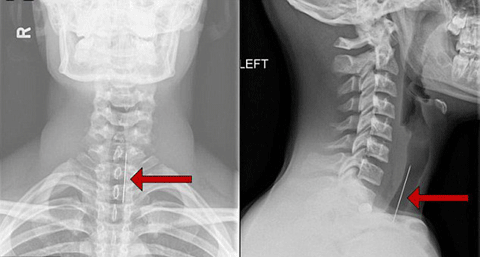

| Phim chụp X - Quang cổ họng cậu bé khiến các bác sĩ vô cùng ngạc nhiên |

Hành động ngốc ngếch của cậu đã khiến cậu nuốt một chiếc phi tiêu. Sau khi chiếc phi tiêu quái ác này cứ mắc kẹt trong cổ họng cậu, mọi người đã đưa cậu tới bệnh viện cấp cứu. Các bác sĩ đã vô cùng ngạc nhiên khi phát hiện một vật có dạng que hình nhọn mắc kẹt trong cổ họng của cậu.